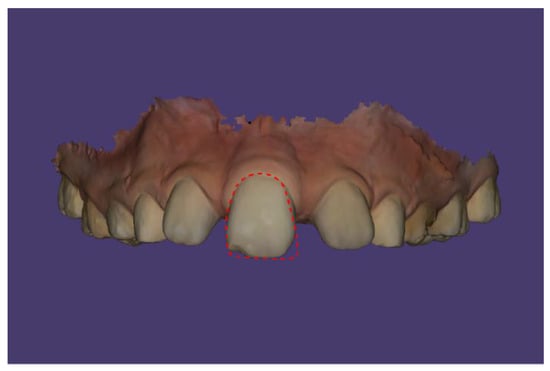

Case Description